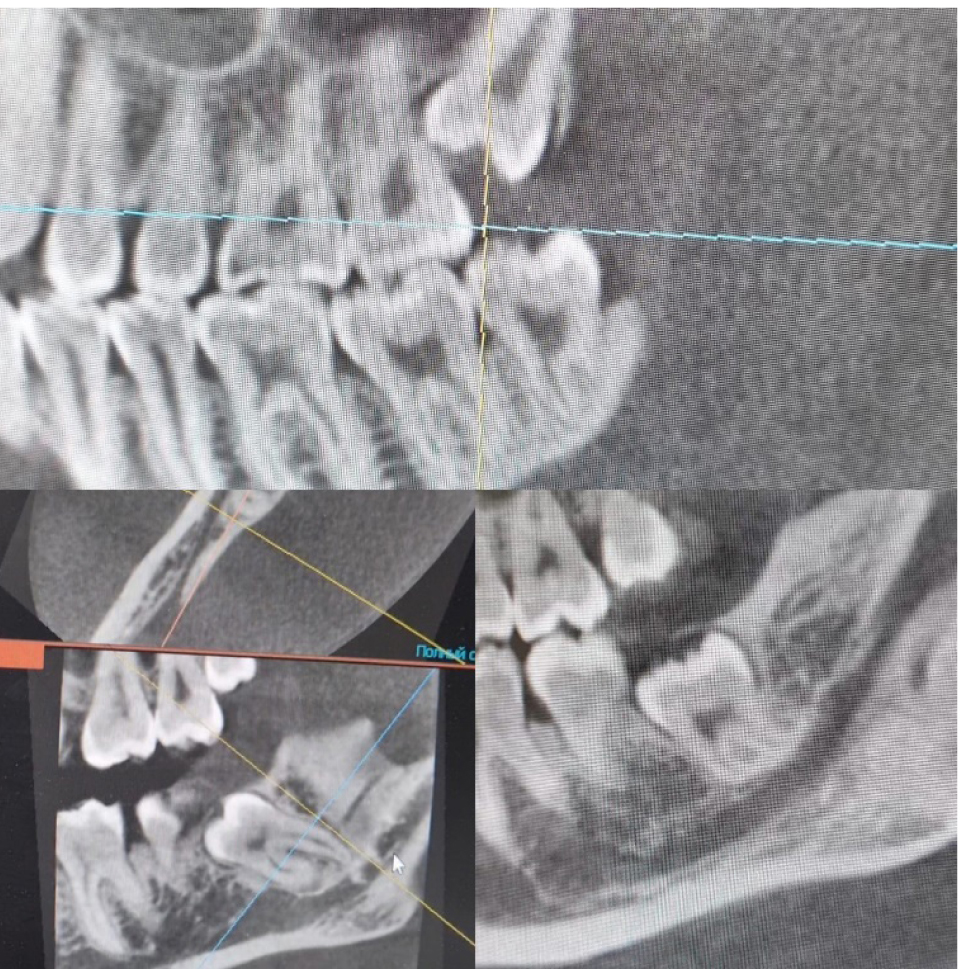

Рис. 1. Конусно-лучевая компьютерная томография

Дополнительные методы обследования включали в себя проведение конусно-лучевой компьютерной томографии (рис. 1), измерение расстояния между центральными резцами нижней и верхней челюсти (рис. 2), для оценки функционального состояния жевательных мышц было проведено электромиографическое исследование.